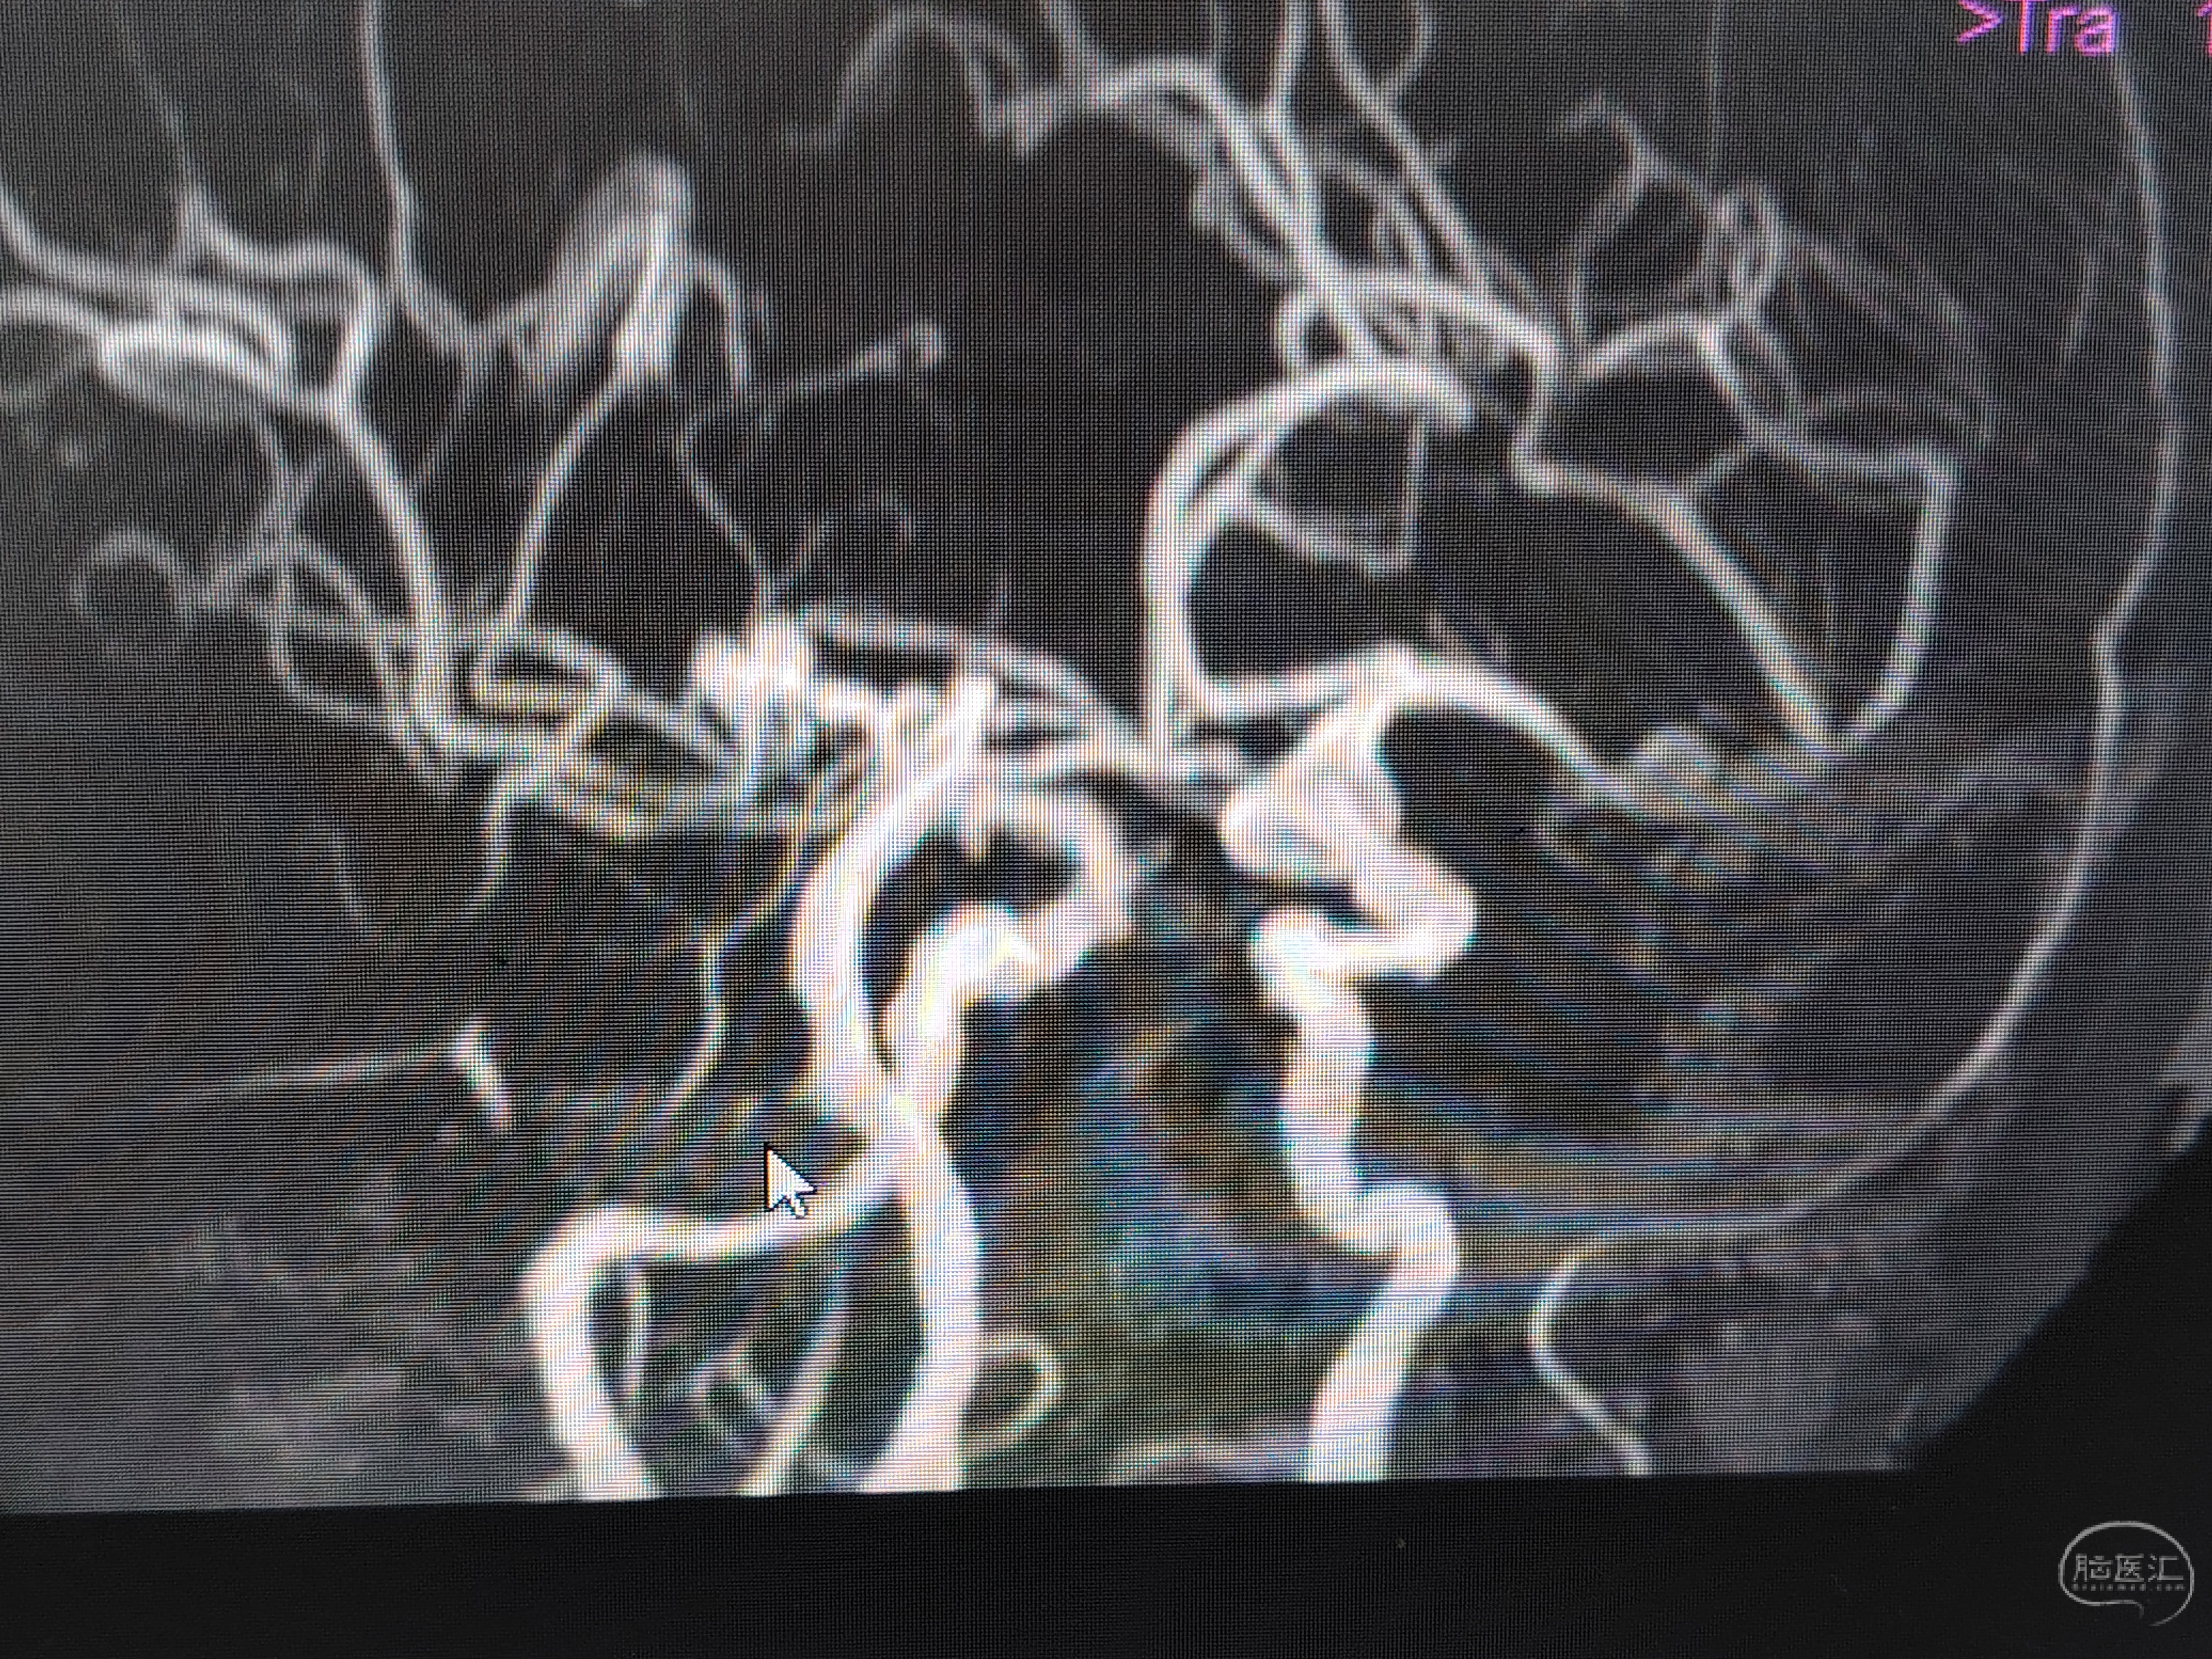

发病前MRA示颅内多发动脉瘤。

急症CTA颅内血管不显影。